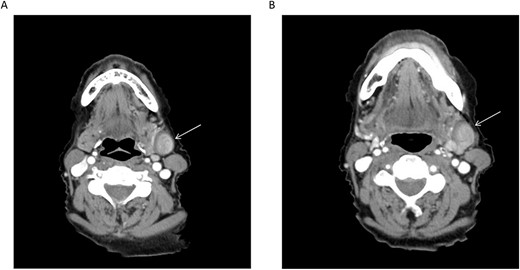

An 80-year-old female was referred to the otolaryngology clinic by her primary care provider with the chief complaint of bilateral intermittent otalgia. During the encounter, the patient recalled mild, left submandibular neck edema associated with tenderness that would resolve in 2–3 days. These symptoms were long-standing and were deteriorating several months prior to her presentation to our office. The patient presented with a computed tomography (CT) ordered by her primary care provider, which revealed a hyperdense mass within the left submandibular gland measuring 1.8 cm anterior–posterior, 1.4 cm transverse and 1.8 cm in height (Fig. 1). This finding raised concern for a primary neoplasm of the left submandibular gland and she was subsequently referred to our clinic.

(A, B) Axial CT cuts of the neck with contrast revealing the lesion in the left submandibular neck (arrow); retrospective review demonstrates communication of the lesion with the adjacent left external jugular vein.